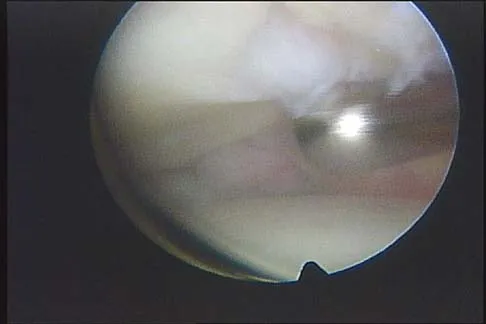

Figure 43 shows an arthroscopic view of a right shoulder through a lateral portal in the beach chair position. The arrow is pointing to what structure?

Explanation

This view from the lateral portal shows a full-thickness rotator cuff tear. The glenohumeral joint can be visualized through this tear. The glenoid, labrum, and biceps tendon attaching to the superior aspect of the glenoid are easily viewed from this portal, and the arrow is pointing to the biceps tendon. Arthroscopic rotator cuff repair can be performed while visualizing from this portal and using anterior and posterior working portals. Mazzocca AD, Noerdlinger M, Cole B, et al: Arthroscopy of the shoulder: Indications and general principles of techniques, in McGinty JB (ed): Operative Arthroscopy, ed 3. Philadelphia, PA, Lippincott Williams & Wilkins, 2003, pp 412-427.